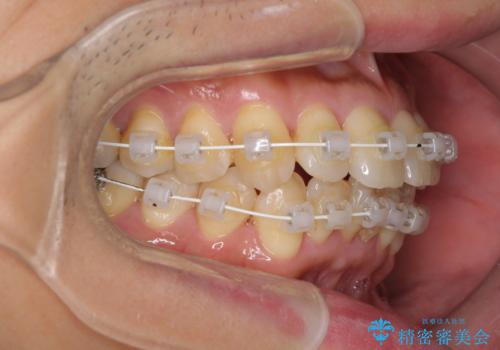

- 矯正装置

- 審美装置

- 治療期間

- 1年3ヶ月

治療開始の頃は、食事や歯磨きが慣れず、装置が頻繁に脱落しましたが、2,3ヶ月ほどで慣れ、その後は1年ほどで治療を終えることができました。